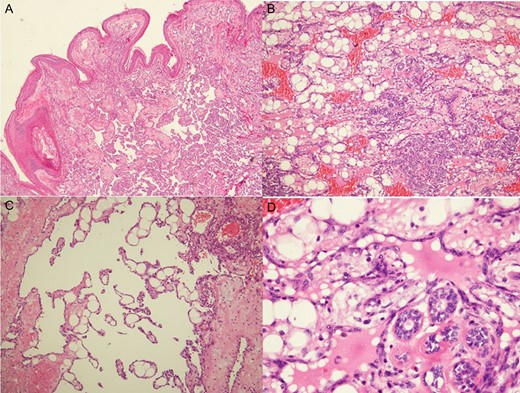

Histologic examination showed a high-grade angiosarcoma in the breast parenchymal section. The poorly differentiated component comprised easily recognizable malignant cells forming infiltrative solid cellular areas (A), with spindled-to-epithelioid pleomorphic hyperchromatic nuclei and abundant eosinophilic cytoplasm intermingled with anastomosing vascular channels (B). In addition, there were blood lakes, necrotic foci (C) and numerous mitoses (D), as well as endothelial multilayering and papillae (E) identifiable in the poorly differentiated areas.